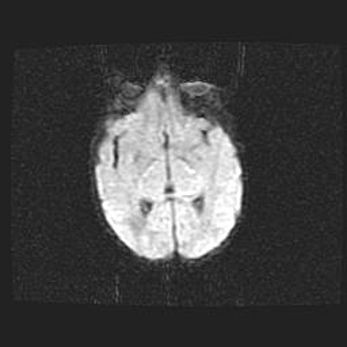

Неполная лизэнцефалия (пахигирия). Открытая гидроцефалия.

Возраст: 17 дней

Вес: 3110 г

Пол: мужской

Окружность головы: 33,5 см

Срок гестации: 35-36 недель

Лизэнцефалия—недоразвитие корковой пластинки и мозговых извилин в результате нарушения миграции нейронов коры. Поверхность мозговых полушарий гладкая. Микроскопически выявляется отсутствие нормальных слоев коры и скопление групп нейронов в подкорковом белом веществе.

Пахигирия—уменьшение числа вторичных извилин. В пораженном полушарии нервные клетки образуют толстый недифференцированный слой с неправильно расположенными нервными волокнами и группами гетеротопных клеток. Нервные клетки незрелые. Белое вещество истончено. При этом нередко аномально развит корково-спинномозговой путь.